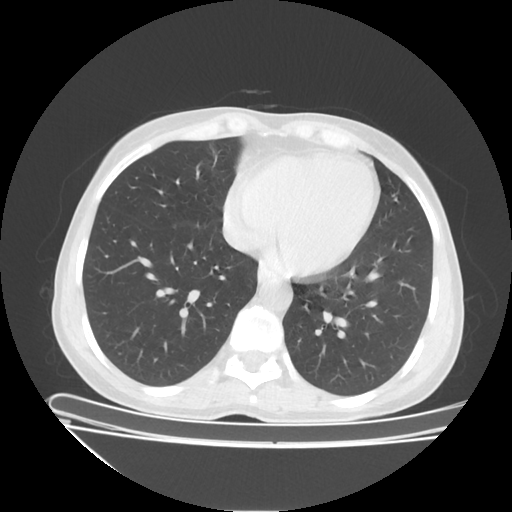

Original VENOUS CT scan

No window - Raw intensity values

Lung window (WL -600, WW 1500 β†’ Low βˆ’1350, High +150)

Mediastinum window (WL 40, WW 400 β†’ Low βˆ’160, High +240)